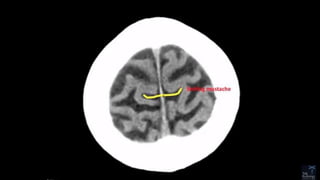

GREY VS WHITE

• The CNS has two kinds of tissue: grey matter and white matter.

• Grey matter contains most of the brain's neuronal cell bodies.[outside]

• White matter is made of axons connecting different parts of grey matter to

each other[inside]

CordBrain

White and grey mater on CT

White and grey mater on MRI

T1 T2